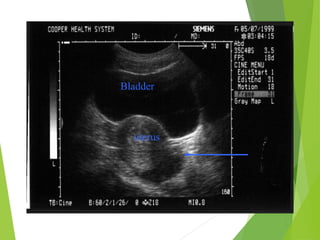

Uterus

 An oval organ located

superior to the full

bladder